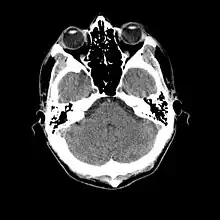

L'examen complémentaire essentiel à l'identification d'une méningite est l'analyse du liquide cérébrospinal obtenu par ponction lombaire[27]. Toutefois une telle ponction est contre-indiquée en cas de masse cérébrale (tumeur, abcès) ou d'hypertension intracrânienne, pouvant entraîner un engagement cérébral. En cas de situation à risque (traumatisme crânien, déficit immunitaire, signe neurologique focal, signe clinique d'hypertension intracrânienne), une imagerie cérébrale préalable est recommandée, avec un scanner ou une IRM[10],[26],[28]. C'est une situation concernant potentiellement environ 45 % des cas adultes[9]. Lorsqu'une imagerie est effectuée avant la ponction ou que celle-ci se montre difficile à réaliser, il est suggéré d'administrer un traitement antibiotique immédiatement afin de ne pas retarder le délai de mise en route du traitement[10], surtout si une telle attente est prévue pour dépasser 30 minutes[26],[28]. Souvent, lorsque l'imagerie n'est pas faite initialement, elle est faite plus tard dans les cas où il existe une complication[3].